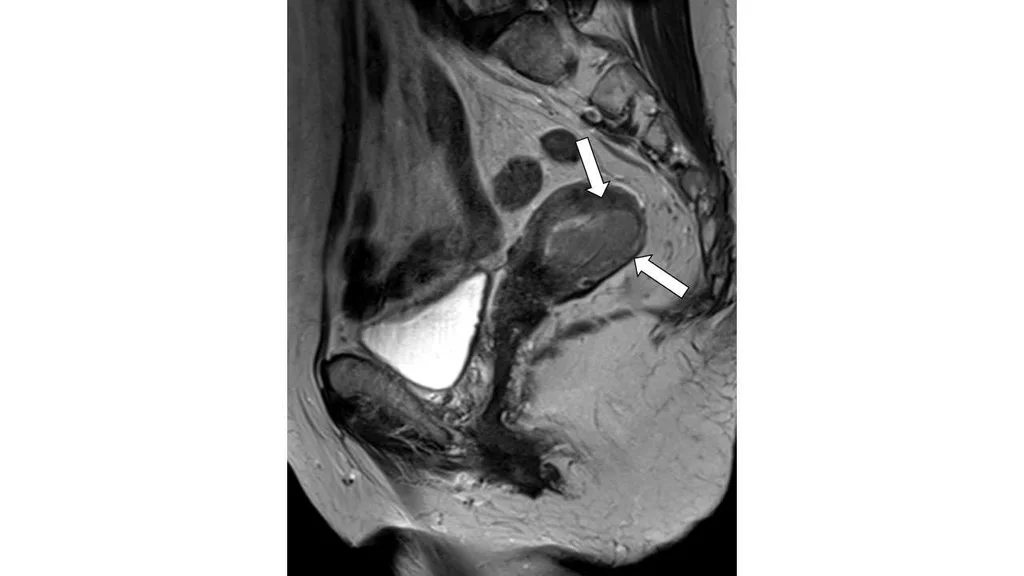

80歲女性,下腹部磁振造影檢查(T2WI)呈現如圖,箭號所指之敘述何者最正確?

詳解

登入後即可查看逐題解析與答題